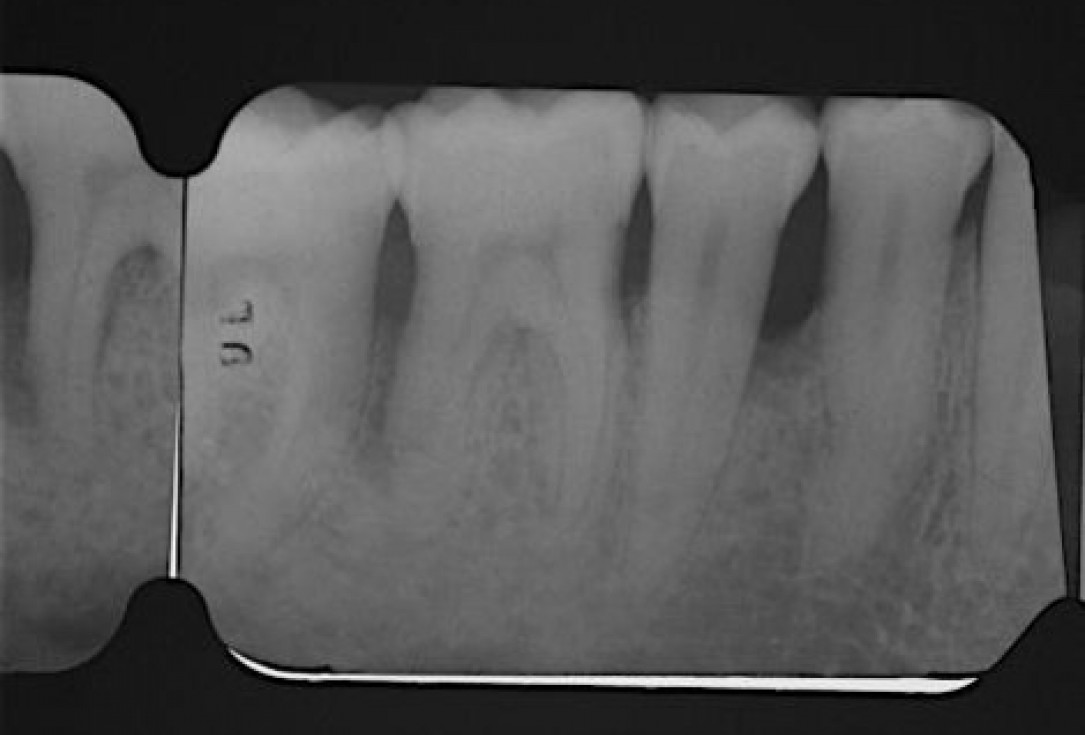

03/22 - Pre-operative radiograph. Deep intrabony defect visible on the distal aspect of tooth 46.

Deep intrabony defects treated using Straumann® Emdogain® - Dr. M. Stefanini